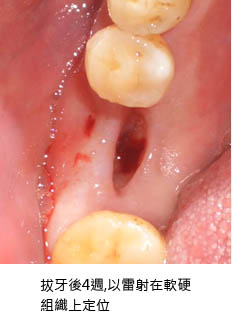

20100702 龍霖醫師

2010-07-02